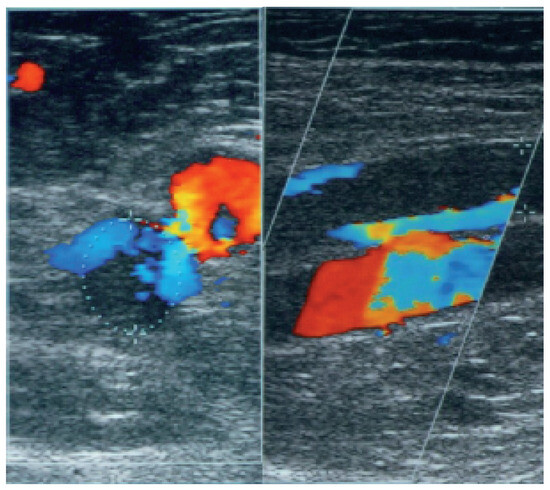

Real-time compression ultrasound (CUS) and colour coded duplex sonography (CCDS) are non-invasive, cheap, easily available screening tools for acute symptomatic proximal DVT with high sensitivity and specifity for proximal symptomatic DVT, ranging from 89 to 100% for both CUS and CCDS, but only 73 to 87% for calf vein thrombosis [21]. One major disadvantage of CUS is that it does not provide acceptable accuracy for iliac or caval thrombosis. CCDS uses full compression of the target vein as principal criterion for the detection of DVT like CUS. CCDS is used at regions with restricted visibility, including the pelvic region or in the calf veins. Its main advantage over CUS is that partial thrombosis with remaining marginal flow can be detected more accurately. Both methods are operator and patient dependent. Figure 2 shows an acute thrombosis with a marginal flow in the femoral vein as visualised by CCDS.

Figure 2.

Superficial vein thrombosis with marginal flow (blue) as presented by colour coded duplexsonography. The neighbouring artery is contrasted in red.